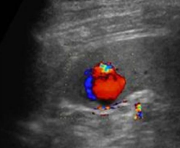

Identify this image.

Splenic infarct